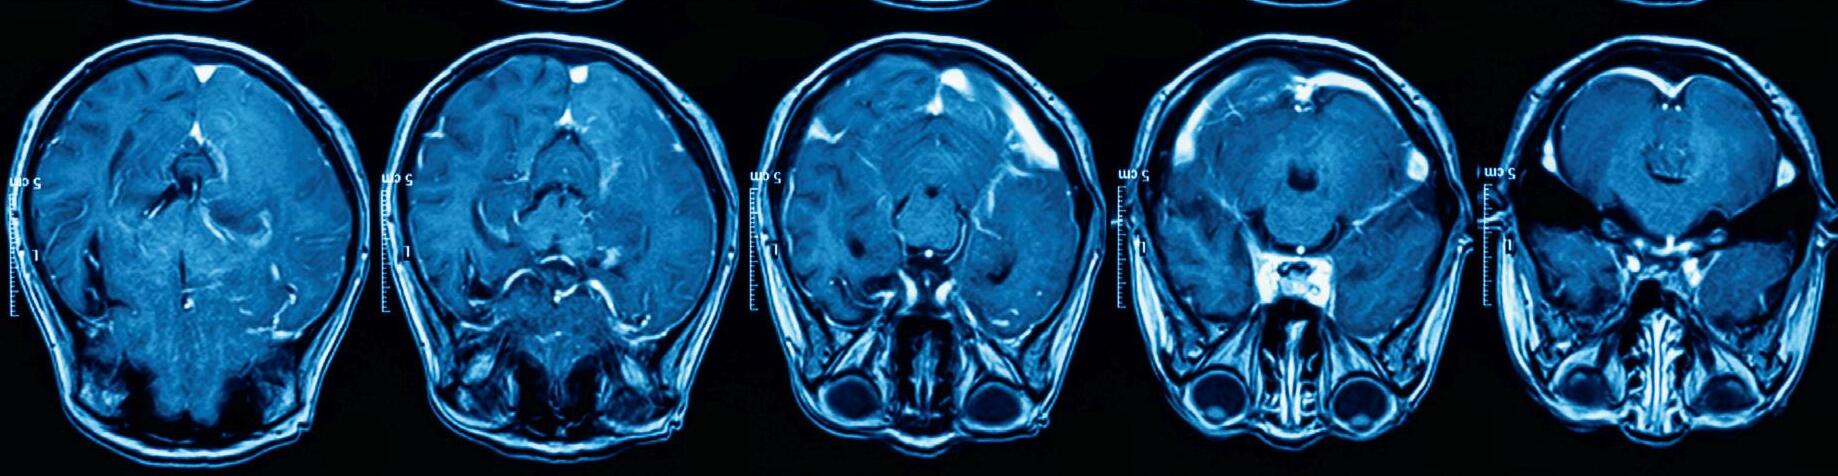

Brain structure and function is changed, so that the brains of traumatised people see the world differently. The effects of

trauma are transdiagnostic, impairing cognition and executive functioning, with a dose-related effect on mental and physical health disorders.

Technology, including functional magnetic resonance imaging (fMRI) and quantitative electroencephalography (QEEG), now enables psychiatrists to examine the organ we treat and to devise effective brain settling methods that repair brain function and heal developmental trauma.